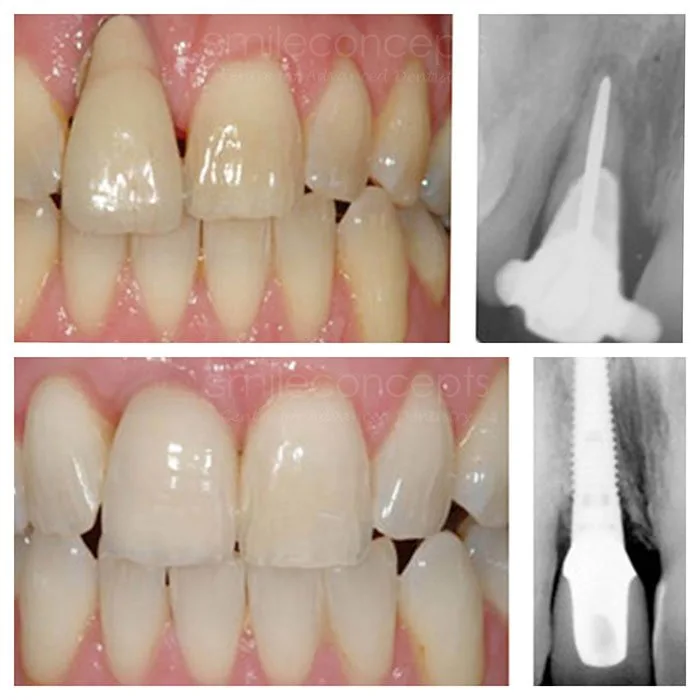

Mark, 59, came to us after three clinics told him he didn’t have enough bone for implants.

After a full 3D scan, we developed a plan using bone grafting and All-on-6 implants. 12 months later, he’s eating steak, smiling in photos, and says: